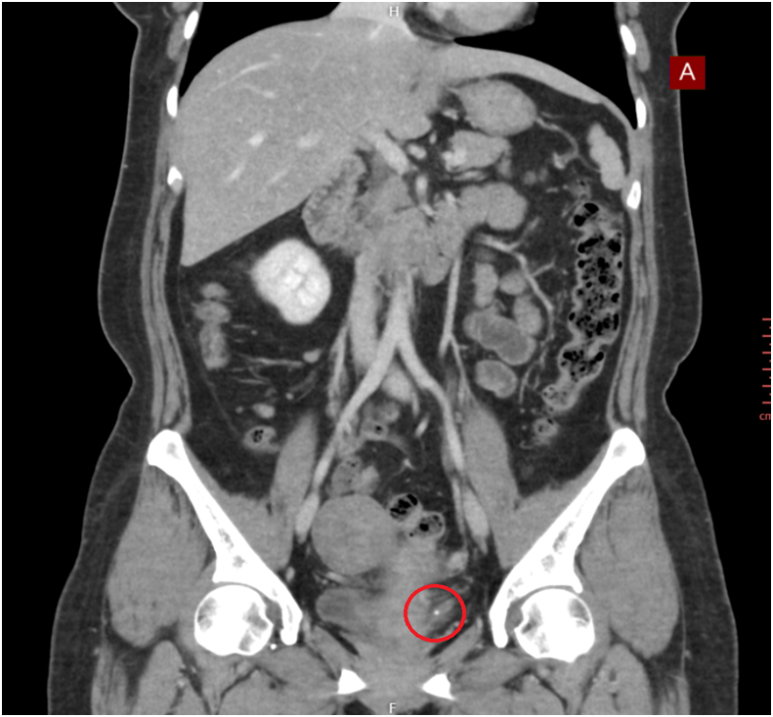

3단계: 영상 검사

복부 초음파: 첫 번째 선택 검사, 충수염, 담석 등 확인

복부 CT: 더 정밀한 진단, 복잡한 경우에 사용